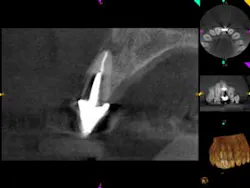

A 52-year-old male patient presented to the office with pain related to tooth No. 9. After radiographic review (figure 4), it was noted that No. 9 had previous endodontic therapy along with a large cast post. The patient was happy with the esthetics of the crown on No. 9, and the clinical and radiographic review showed intact margins and a sound restoration. The recommendation was made to take a narrow-field CBCT image of tooth No. 9. It revealed periapical pathology related to tooth No. 9 that had not broken through the buccal or palatal cortex (figure 5). No fractures were noted and disassembly of the current restoration was not ideal due to the size of the casting in place. The patient was appointed for microsurgical endodontic treatment to save tooth No. 9.

Again, a very minimal osteotomy could be made with the use of an operating microscope. After proper root resection, root-end prep, the placement of a biocompatible bioceramic filling (figure 6), the site is ready to be grafted. The lesion is removed and sent for biopsy, and we are left with a zero-degree bevel to root-end prep, and filling at this point becomes analogous to a Class I restoration. After radiographic verification that we have proper root resection and adequate apical fill, our bone grafting material was placed and final radiographs where taken (figure 7).